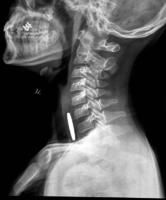

食管放射檢查2.上消化道鋇餐X線檢查:注意有無胃-食管反流、食管裂孔疝或食管狹窄,並了解胃和十二指腸情況。